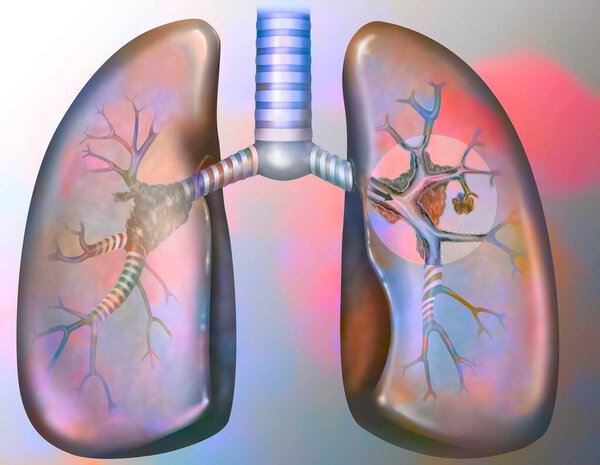

- Рак легких курильщика (с наличием депозитов смолы в бронхах).

Рак легких курильщика (с наличием депозитов смолы в бронхах).

Рак легких курильщика (с наличием депозитов смолы в бронхах).